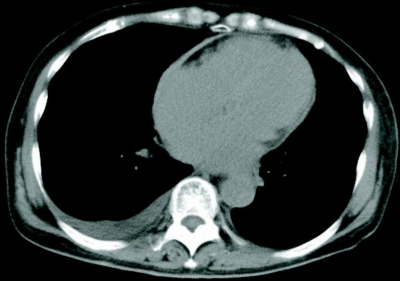

体温 36.5 ℃。脈拍 72/分、整。血圧 110/80 mmHg。呼吸数 14/分。SpO₂ 95 %(room air)。心音は微弱で拡張早期過剰心音を聴取する。呼吸音に異常を認めない。両側に著明な下腿浮腫を認める。胸部 CT及び右心カテーテル所見を別に示す。